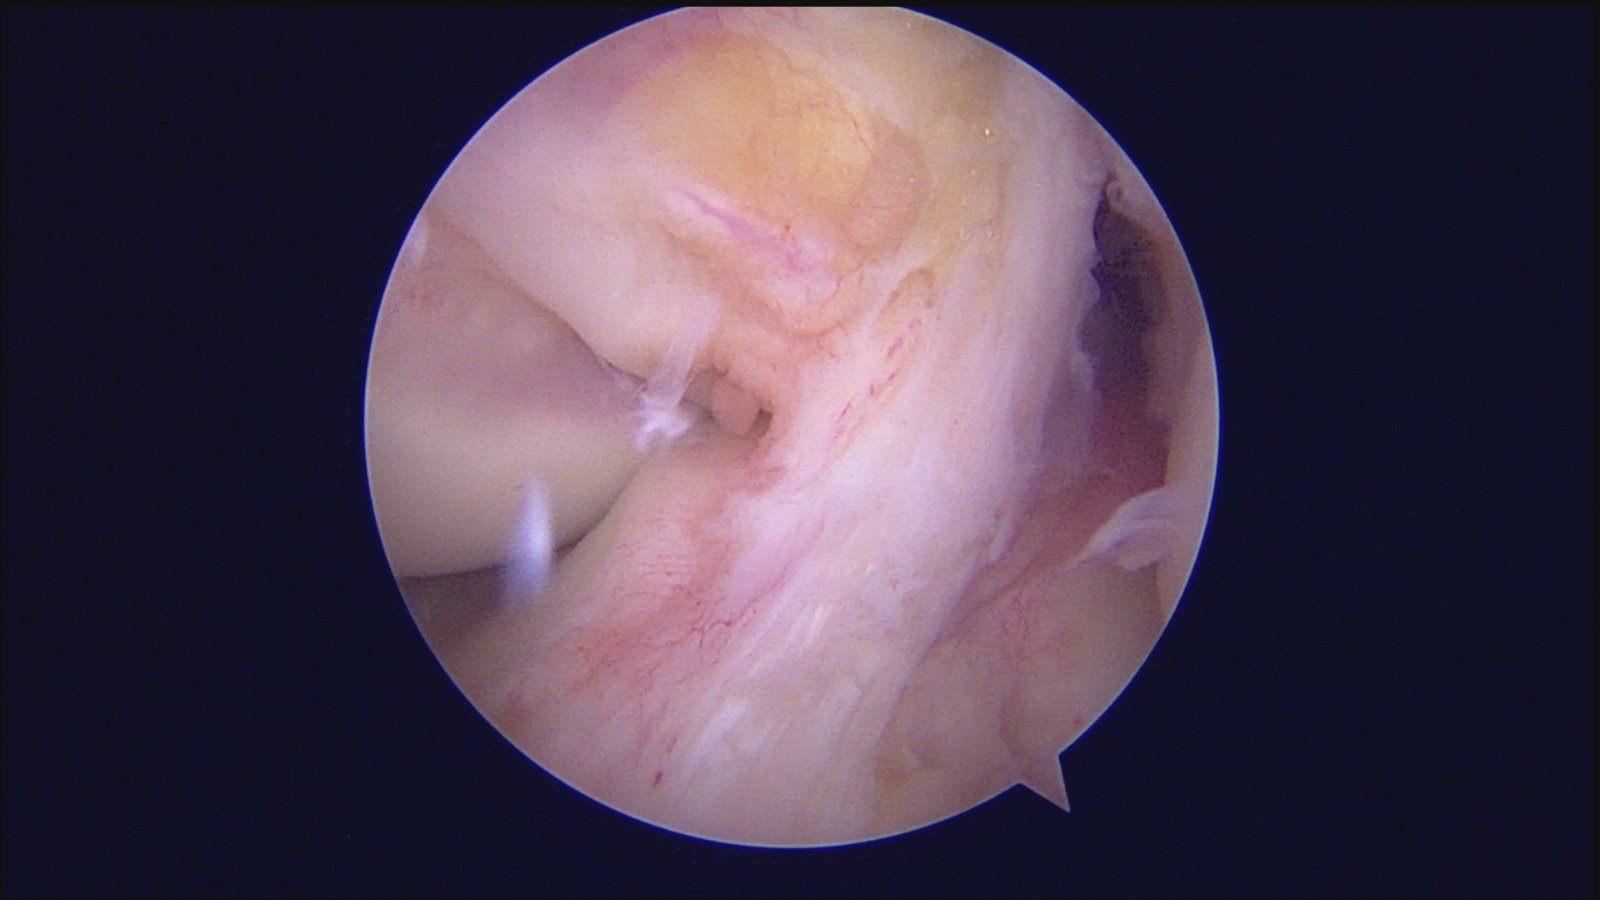

GalleryShoulder rotator cuff repair Meniscus root repair Meniscus repair Bankart repair for recurrent shoulder dislocation ACL reconstruction Machines Instruments